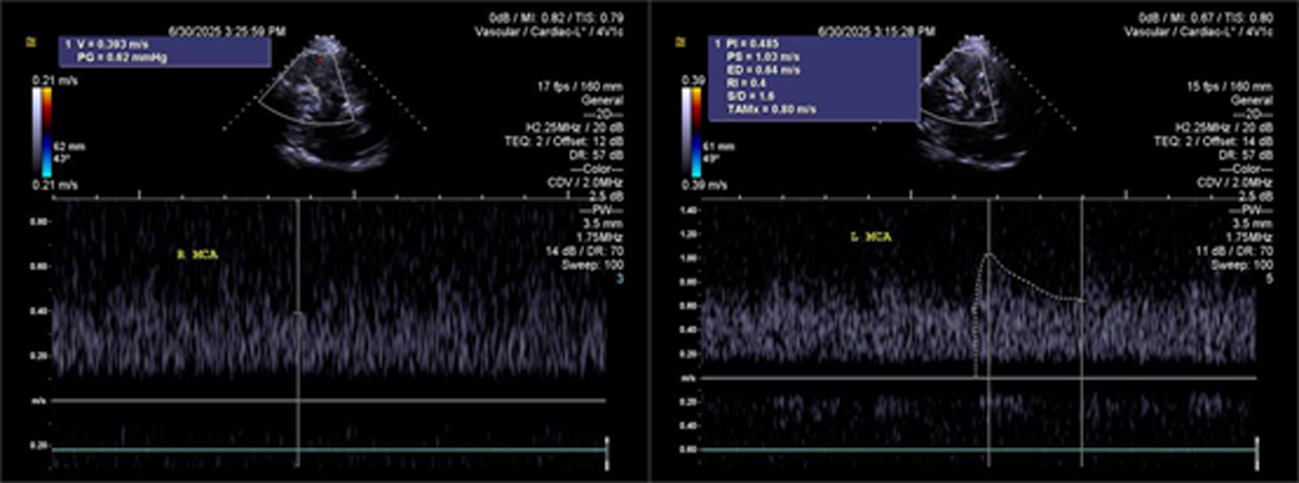

Objective To summarize diagnostic and differentialdiagnostic approaches for initial detection of moyamoya disease (MMD) using carotid ultrasound (CAU). Methods We report two patients who were first diagnosed with MMD by CAU and summarize the diagnostic reasoning and differential considerations. Relevant literature was reviewed to contextualize these findings. Results Case 1: A 57-year-old female presented with a >10 year history of dizziness and headache with recurrence over 3 days. CAU showed a reduced diameter of the left internal carotid artery (ICA), decreased flow velocity, and a lower resistance index, raising suspicion for severe intracranial stenosis or occlusion and prompting clinical exclusion of MMD. Magnetic resonance angiography (MRA) confirmed severe stenosis of the left ICA with absent distal branches and multiple small abnormal vascular networks in the left suprasellar region, consistent with MMD. Case 2: A 23-year-old male presented with dizziness for >1 year and transient right upperlimb weakness for 1 day. CAU and transcranial color Doppler (TCCD) showed a narrowed right ICA with reduced flow velocity and increased resistance index, suggesting chronic occlusion of the right middle cerebral artery and stenosis of the left middle cerebral artery, raising the possibility of MMD. MRA demonstrated an indistinct right ICA and right middle cerebral artery and narrowing of the left middle cerebral artery. On followup, the patient was diagnosed with MMD. Conclusion When CAU reveals a small internal carotid artery diameter accompanied by slowed flow velocity, clinicians should perform a comprehensive evaluation-including TCCD and further vascular imaging-to avoid missed or incorrect diagnoses of MMD.